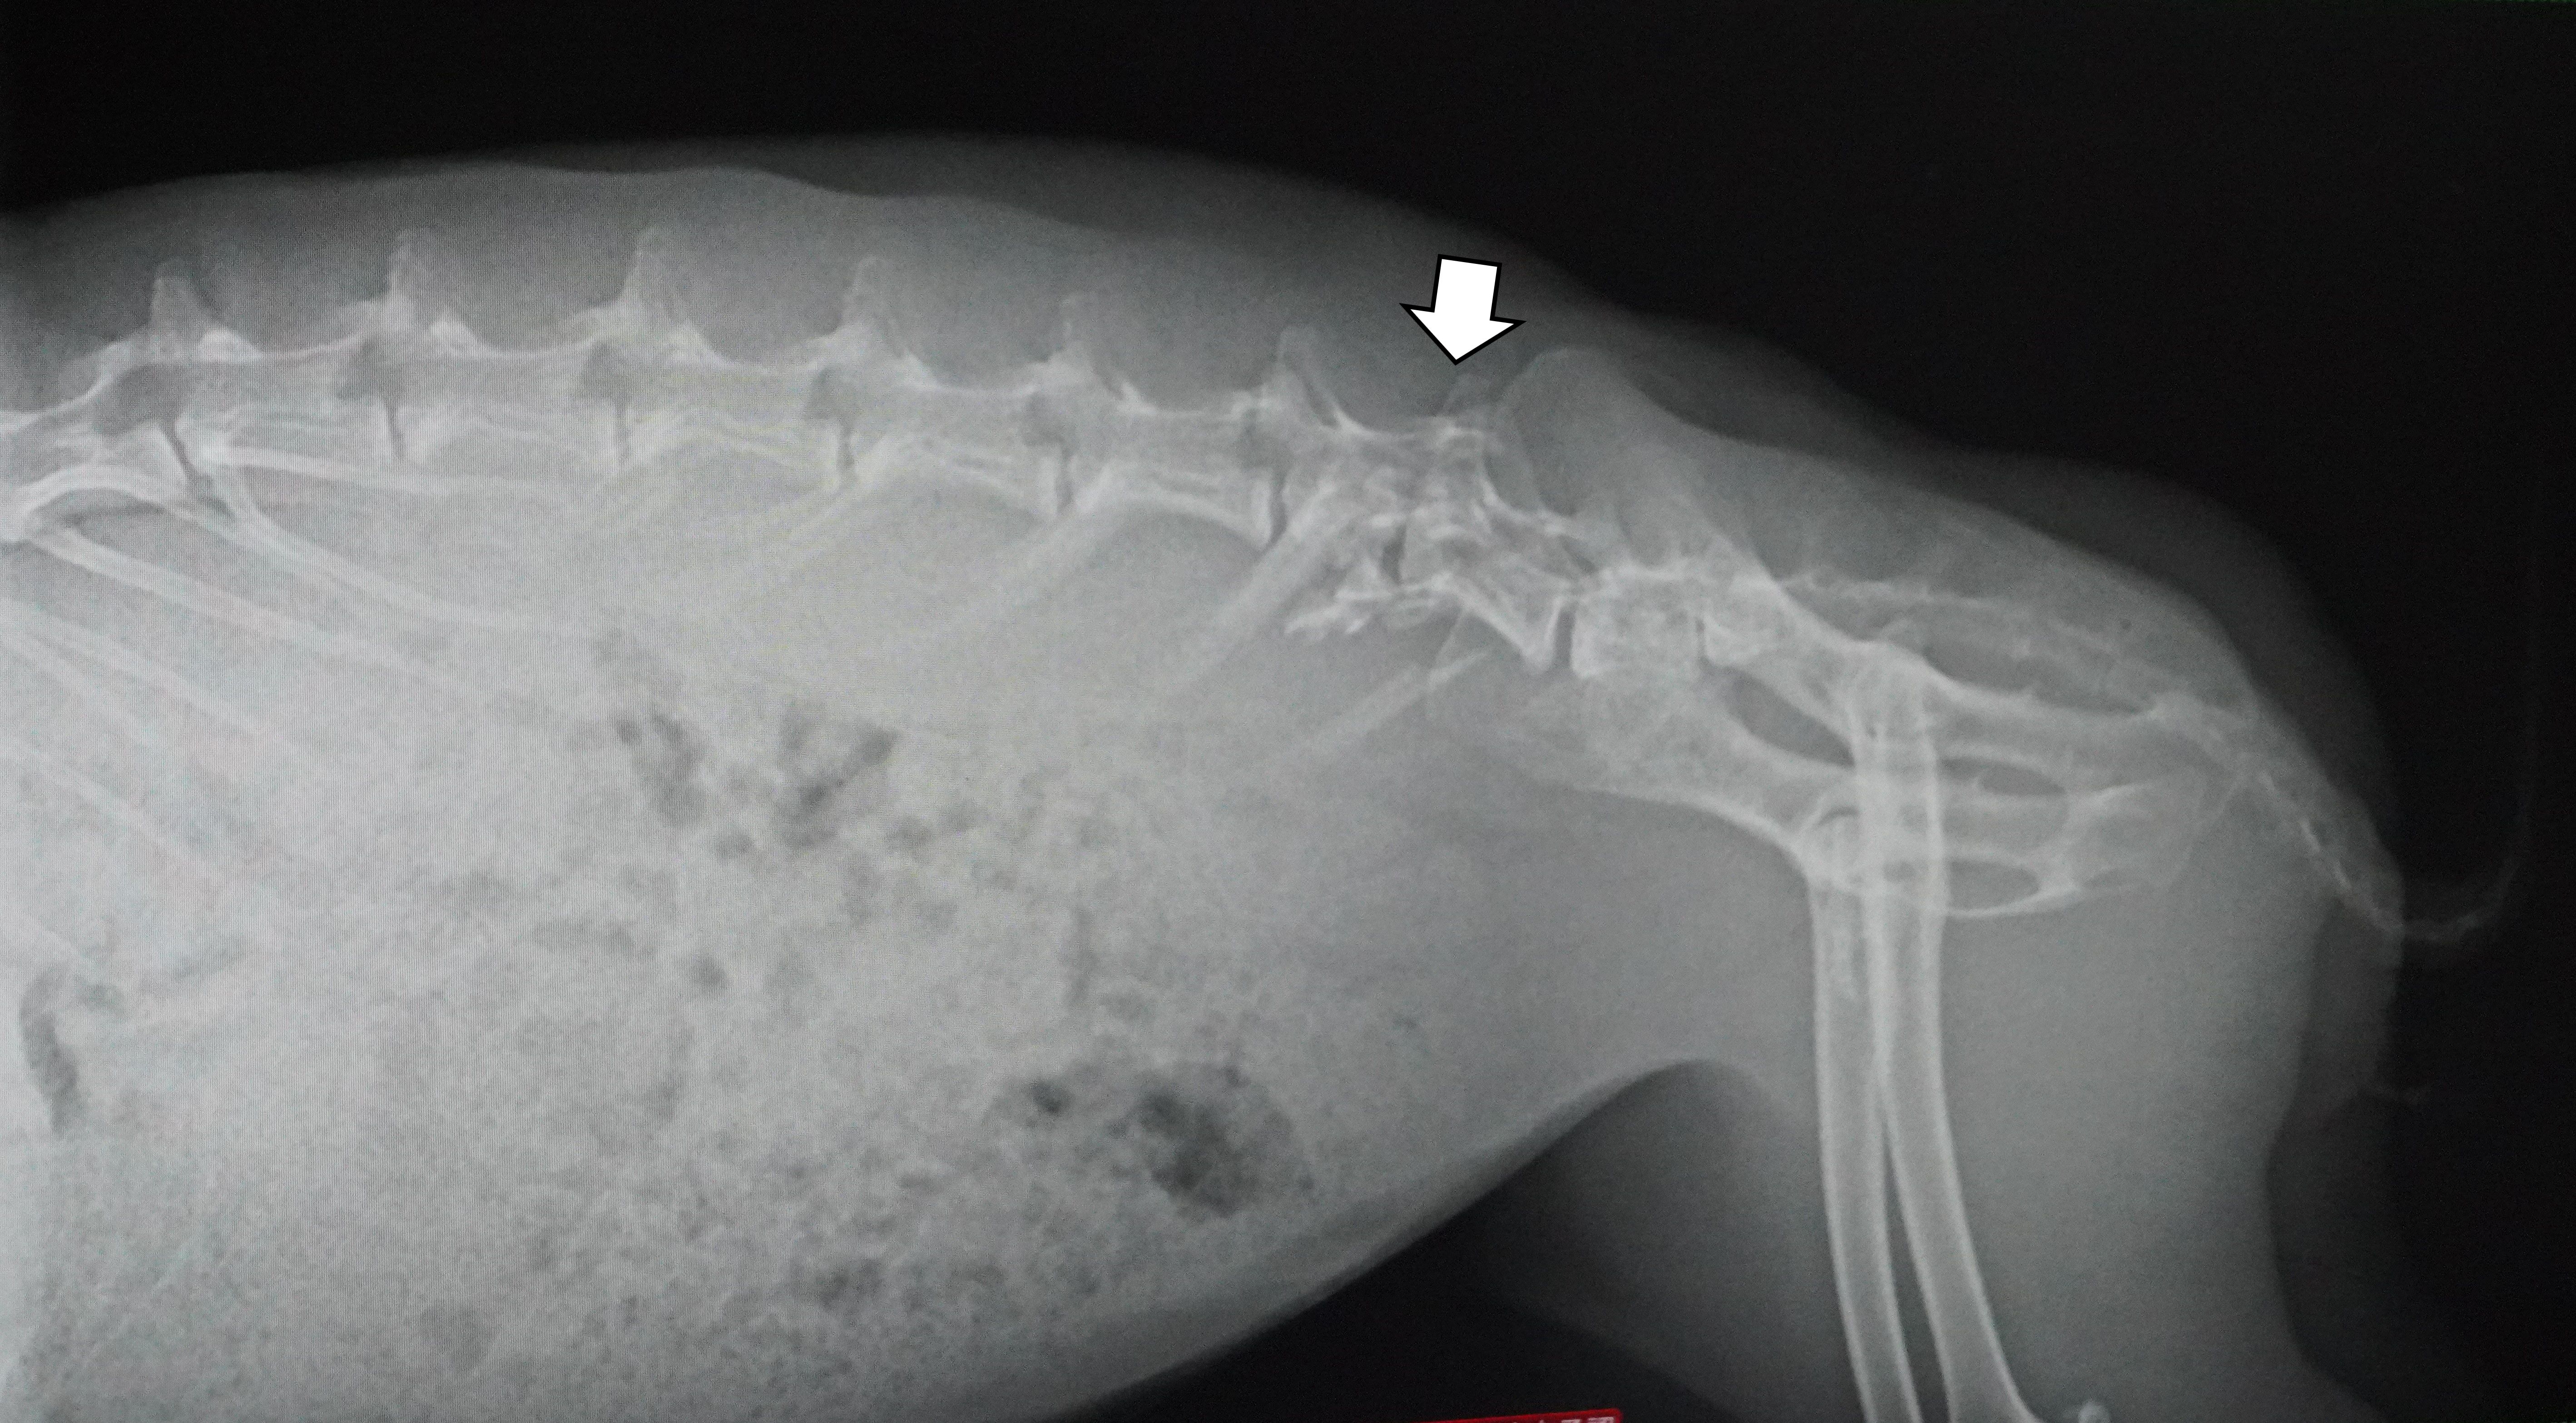

相変わらず、折れた腕は痛そうにしています。